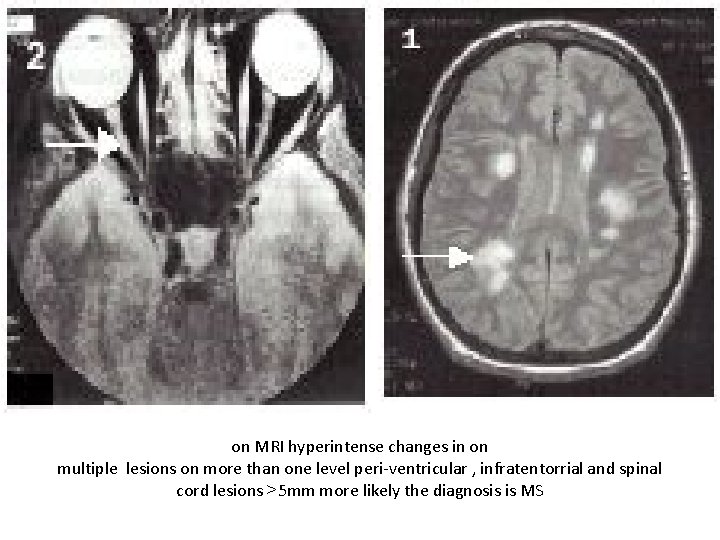

on MRI hyperintense changes in on multiple lesions on more than one level peri-ventricular , infratentorrial and spinal cord lesions >5 mm more likely the diagnosis is MS